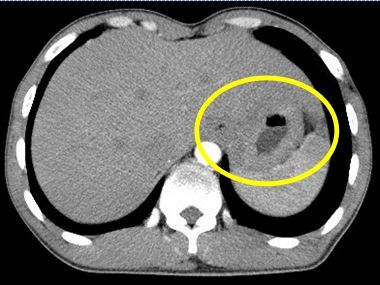

Chụp cắt lớp CT

CT scan giúp đánh giá tốt tình trạng thương tổn của dạ dày, sự xâm lấn của khối u đến các bộ phận xung quanh. Vì vậy, nó cũng được sử dụng trong một số trường hợp tầm soát ung thư dạ dày.